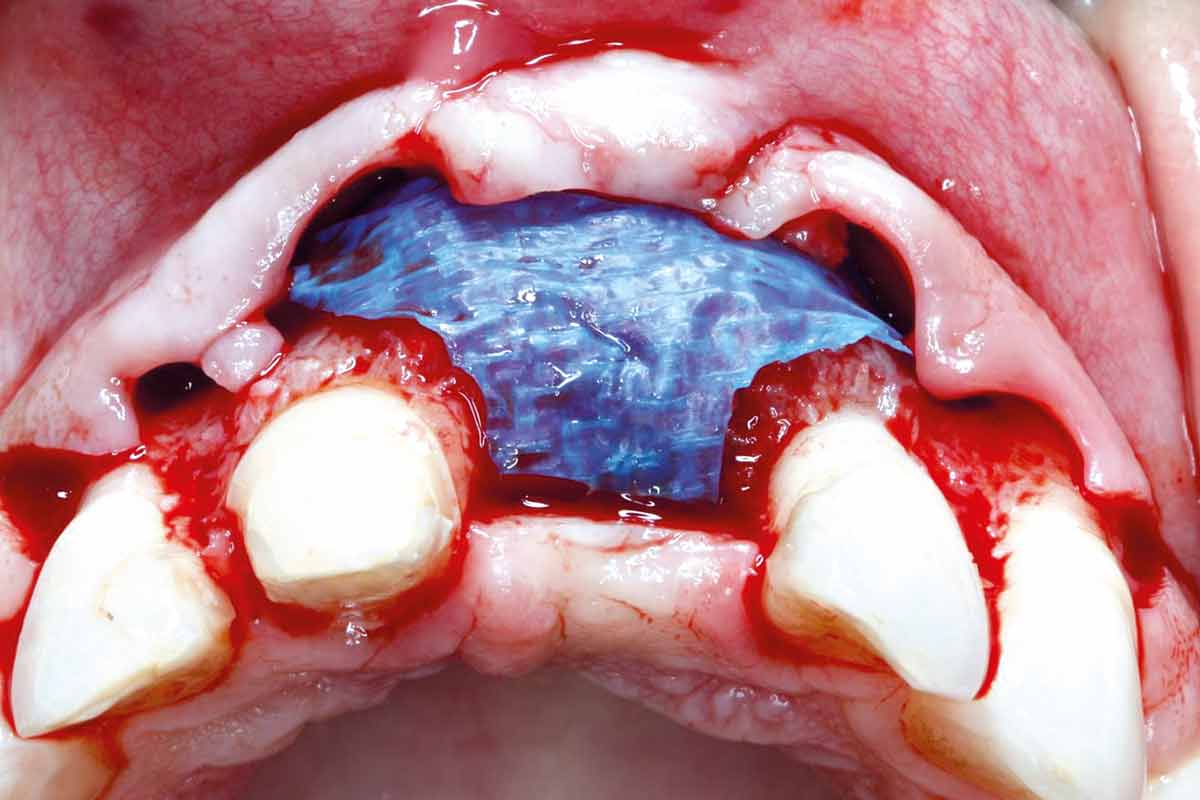

Implant placement and bone augmentation in the aesthetic zone using maxgraft® and permamem® - Dr. A. Puišys

Implant placed in the deficient site. permamem® in place for covering.

Initial situation – Treatment plan: Replace the adhesive upper left central incisor bridge with a dental implant